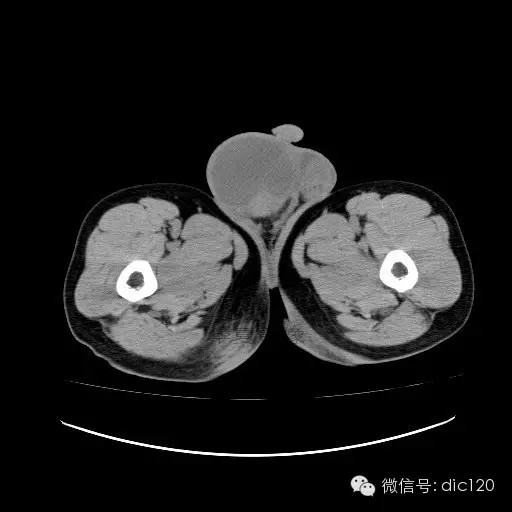

【影像表现】

青年男性,右侧睾丸肿大,边界清晰,增强后睾丸不均匀中度强化,内可见多灶囊变坏死区,动脉期肿块内有细小动脉血管显示,延迟期可见分隔样强化,鞘膜囊可见积液。

定位定性:右侧睾丸恶性肿瘤。

【影像诊断】

右侧睾丸精原细胞瘤,右侧睾丸鞘膜积液。